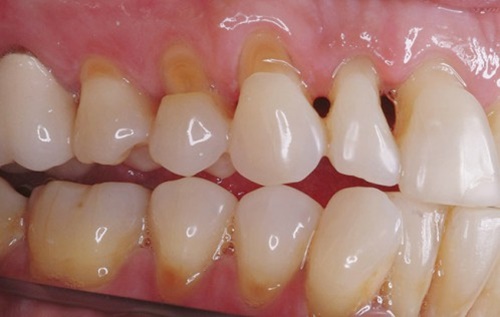

Xuất hiện những rãnh khuyết hình chữ V ở 1/3 cổ răng, gần đường viền nướu, nó cũng có thế xảy ra với mặt nhai của răng hoặc giữa các răng.

Nghiêm trọng hơn, ngà răng bên trong men răng có thể bị lộ ra.